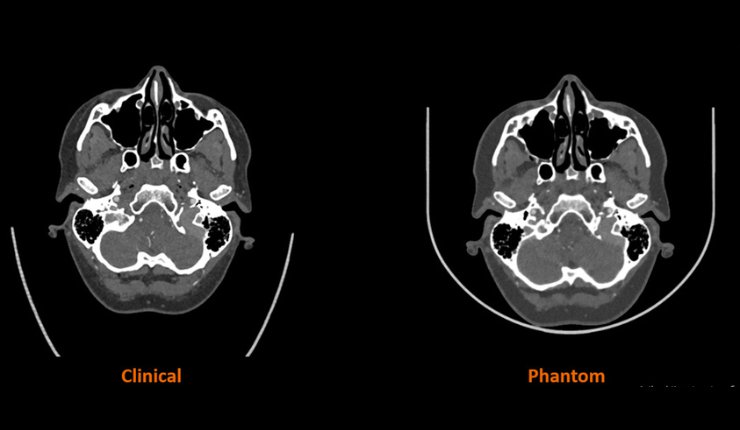

Stratasys has announced that it has partnered with Siemens Healthineers to carry out a landmark research project designed to develop new state-of-the-art solutions for the advancement of medal imaging phantoms for computed tomography (CT) imaging.